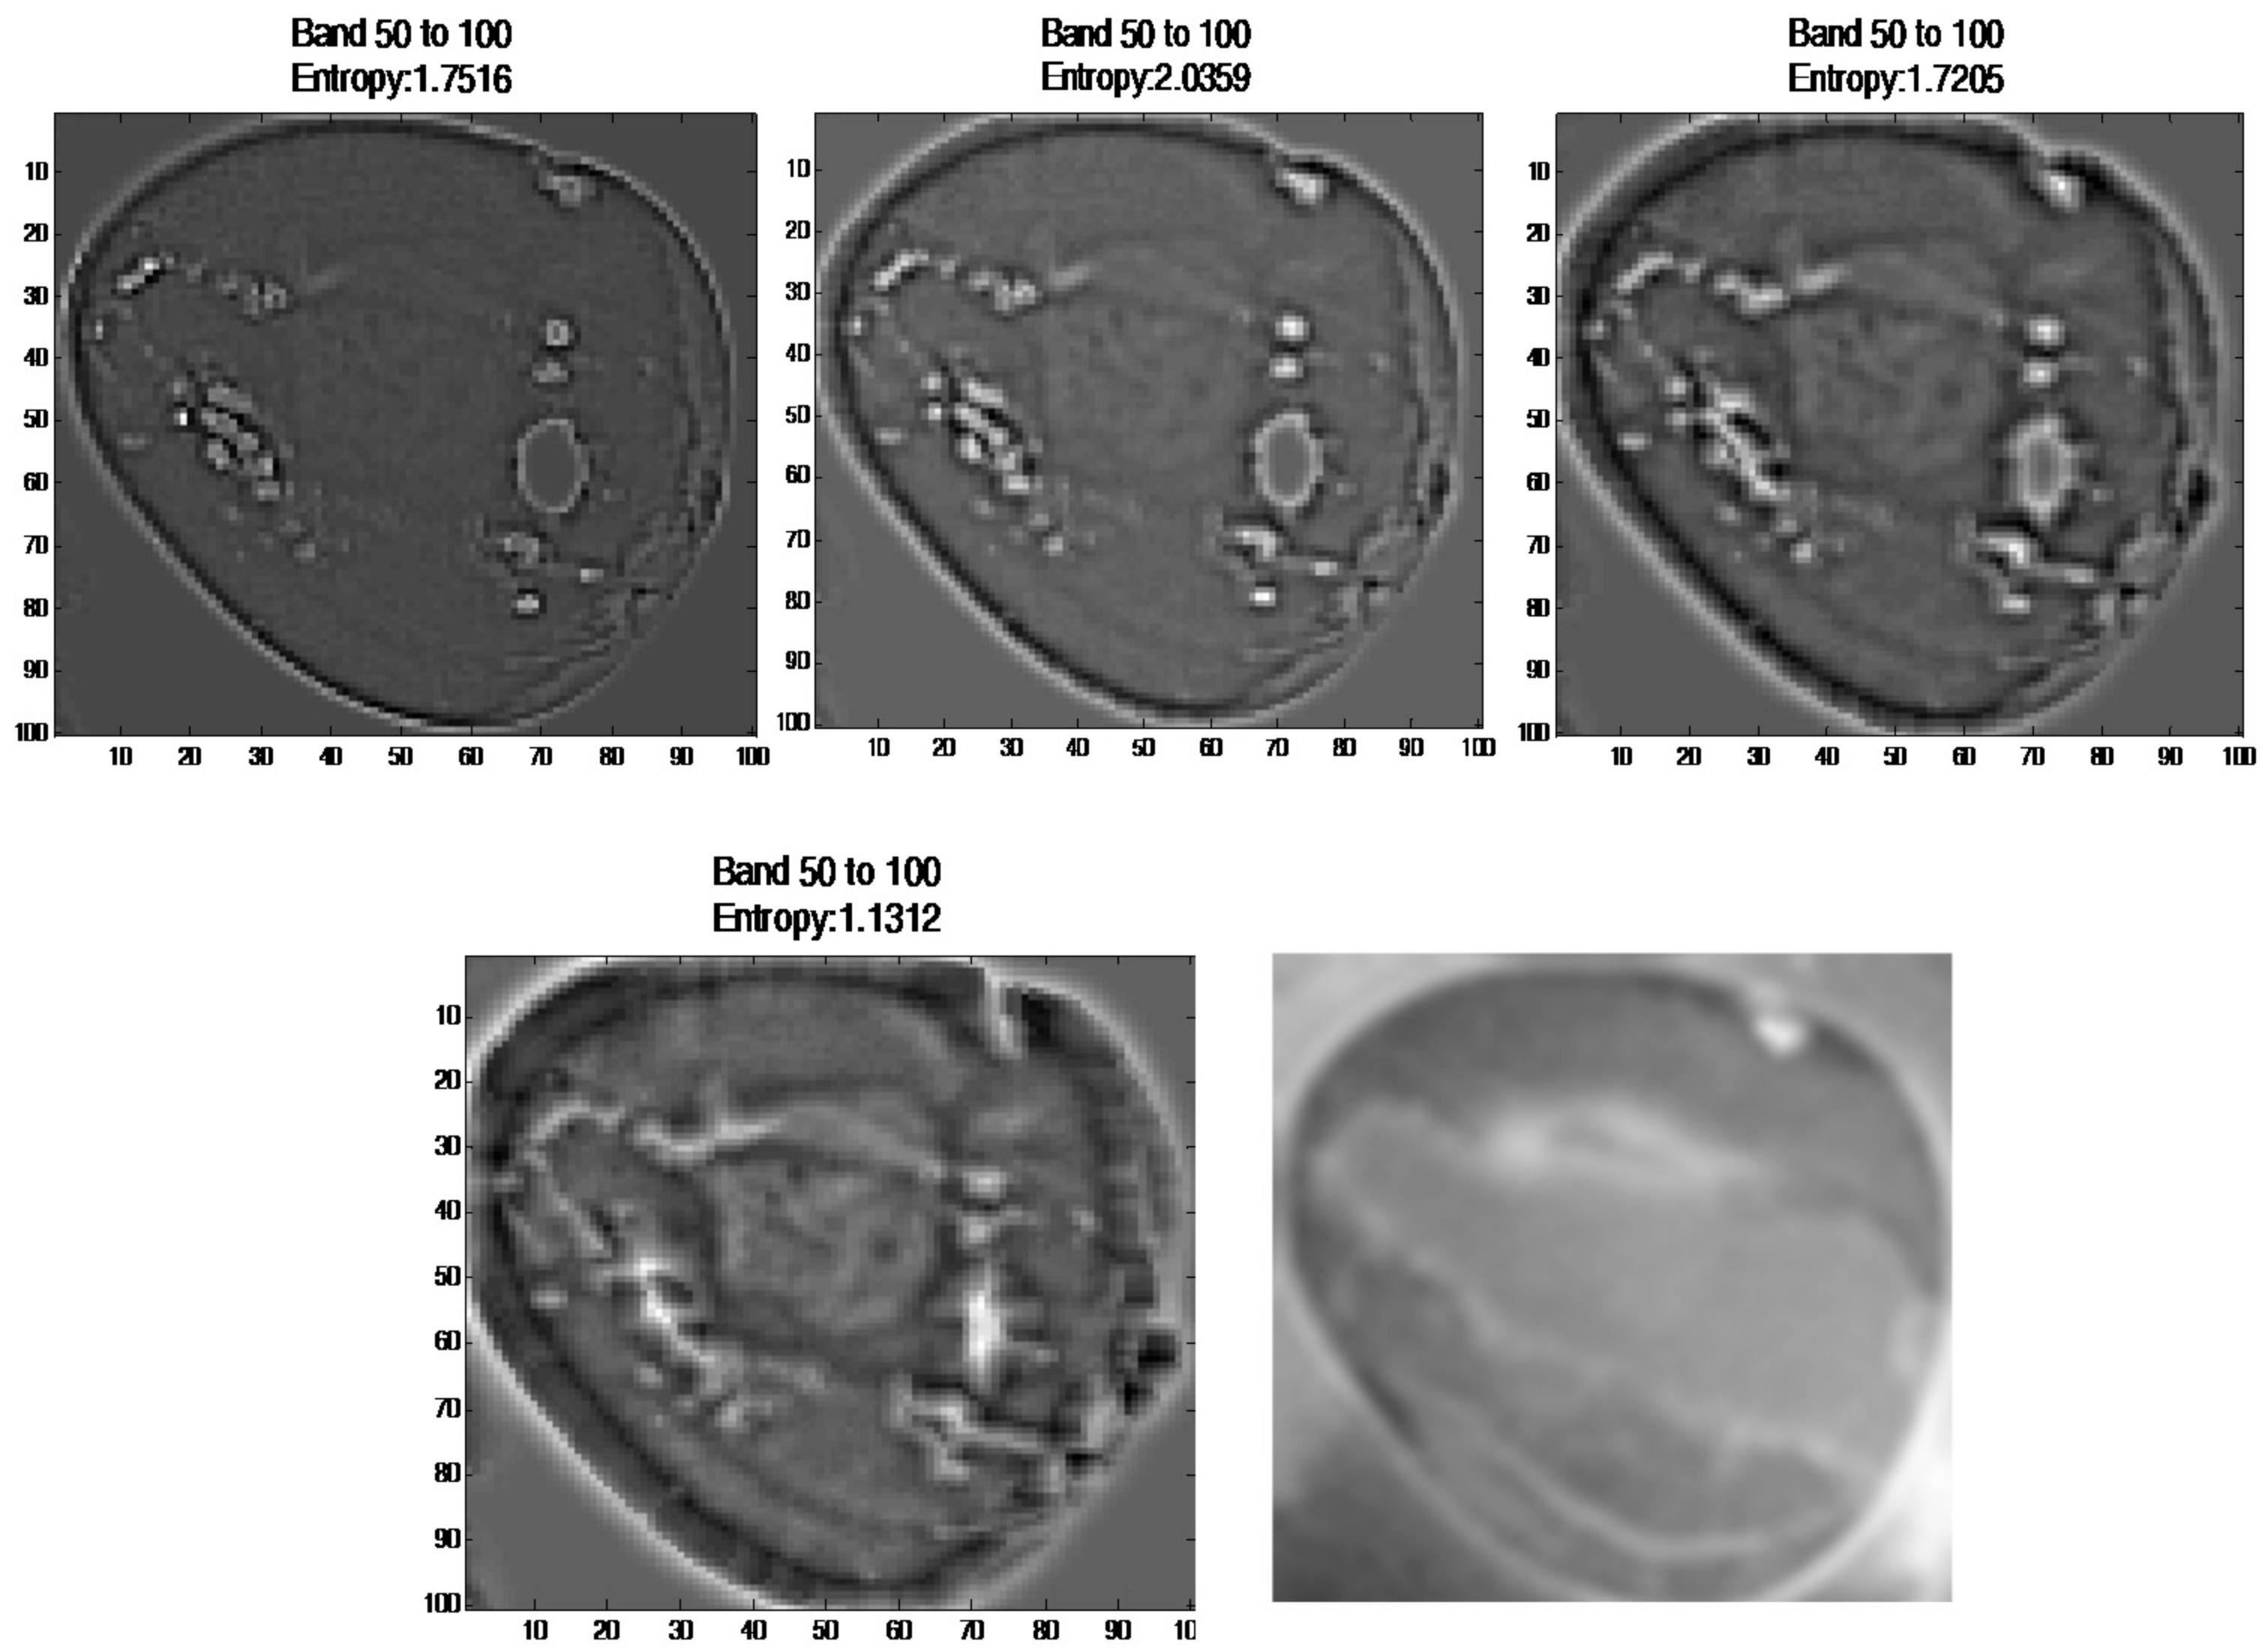

3.2.6. Image Subtraction